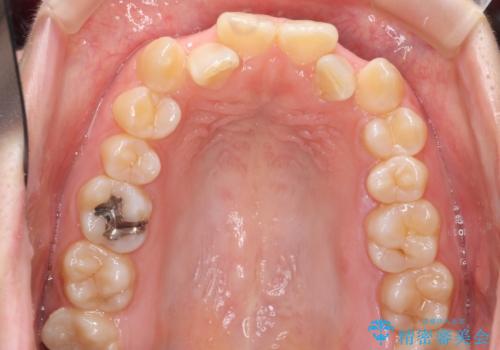

プラン1:上の正中をずらさない・・・上下左右4本抜歯

プラン2:上の正中は少し左にずれる・・・左の上下2本抜歯

を提案し、プラン2を選択されました。

最小限の抜歯により矯正ができたと、喜んでいただきました。